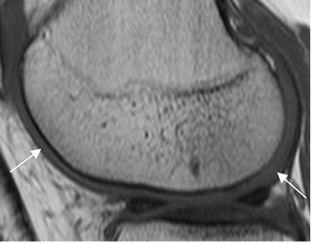

La RM es la técnica de elección para valorar el cartílago articular. Igualmente es un excelente método, para valorar los tejidos blandos y las alteraciones sinoviales. (2).

(Fig 4).

Fig 4. Cartílago articular normal.

RM T1 sagital. Cartílago normal, cubriendo el cóndilo femoral.